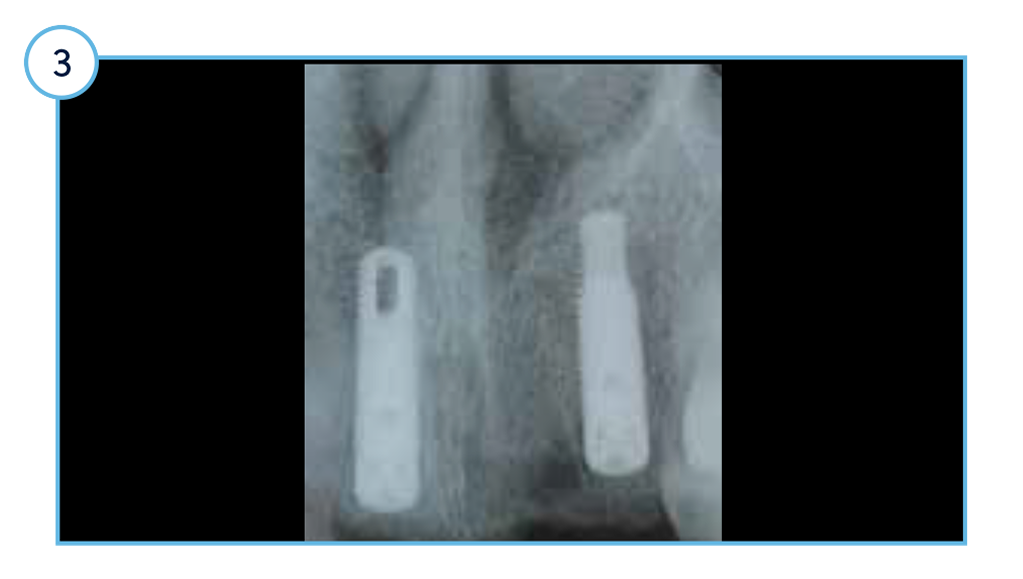

Case Study: Immediate Placement of TSVT Dental Implants

Clinical view of the aesthetic outcome one-year post restoration.